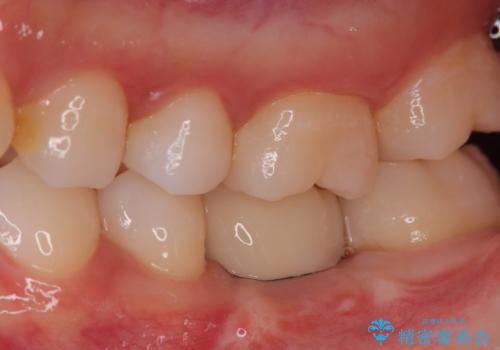

奥歯が残せないと言われた。『インプラント治療』

歯のなかったところをインプラント治療を行うことによってまた噛める喜びを感じていただけて良かったと思っております。